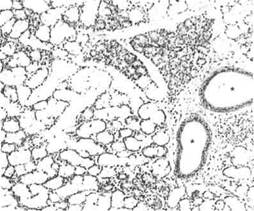

Подъязычная железа, Г. Э.

Два крупных выводных протока (звездочки) проходят в строме железы. Они выстланы многослойным эпителием, что указывает на эктодермальное происхождение железы.